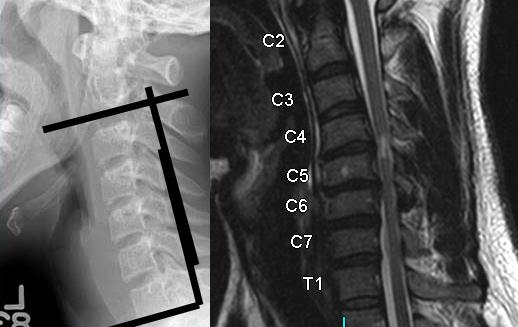

The imaging studies show a type II odontoid fracture, a congenital fusion at C2/3 and C4/5, and a large soft disc herniation at C3/4 with spinal cord compression and myelomalacia.

9. A 67-year-old man falls forward from standing height sustaining a hyperextension injury to his neck. He has neurological deficits present on physical examination. A radiograph, CT scan and MRI are seen in Figures A, B and C. Which of the following MOST likely characterizes his neurologic examination?"

DISCUSSION: The patient in the scenario has a central cord syndrome. The images show a relatively kyphotic spine with moderate osteophyte formation from C4 through C6. The MRI shows stenosis without cord signal change. Central cord syndrome is characterized by motor deficits more pronounced in the upper extremities than lower extremities. In addition, finger and wrist motor function is more affected than shoulder and biceps function. Sensory deficits are usually minimal.

Nowak et al reviewed central cord syndrome. It is the most common incomplete spinal cord injury, typically resulting from an extension injury. It presents as a spectrum from hand weakness to quadraparesis with sacral sparring. Early surgical treatment is still controversial.